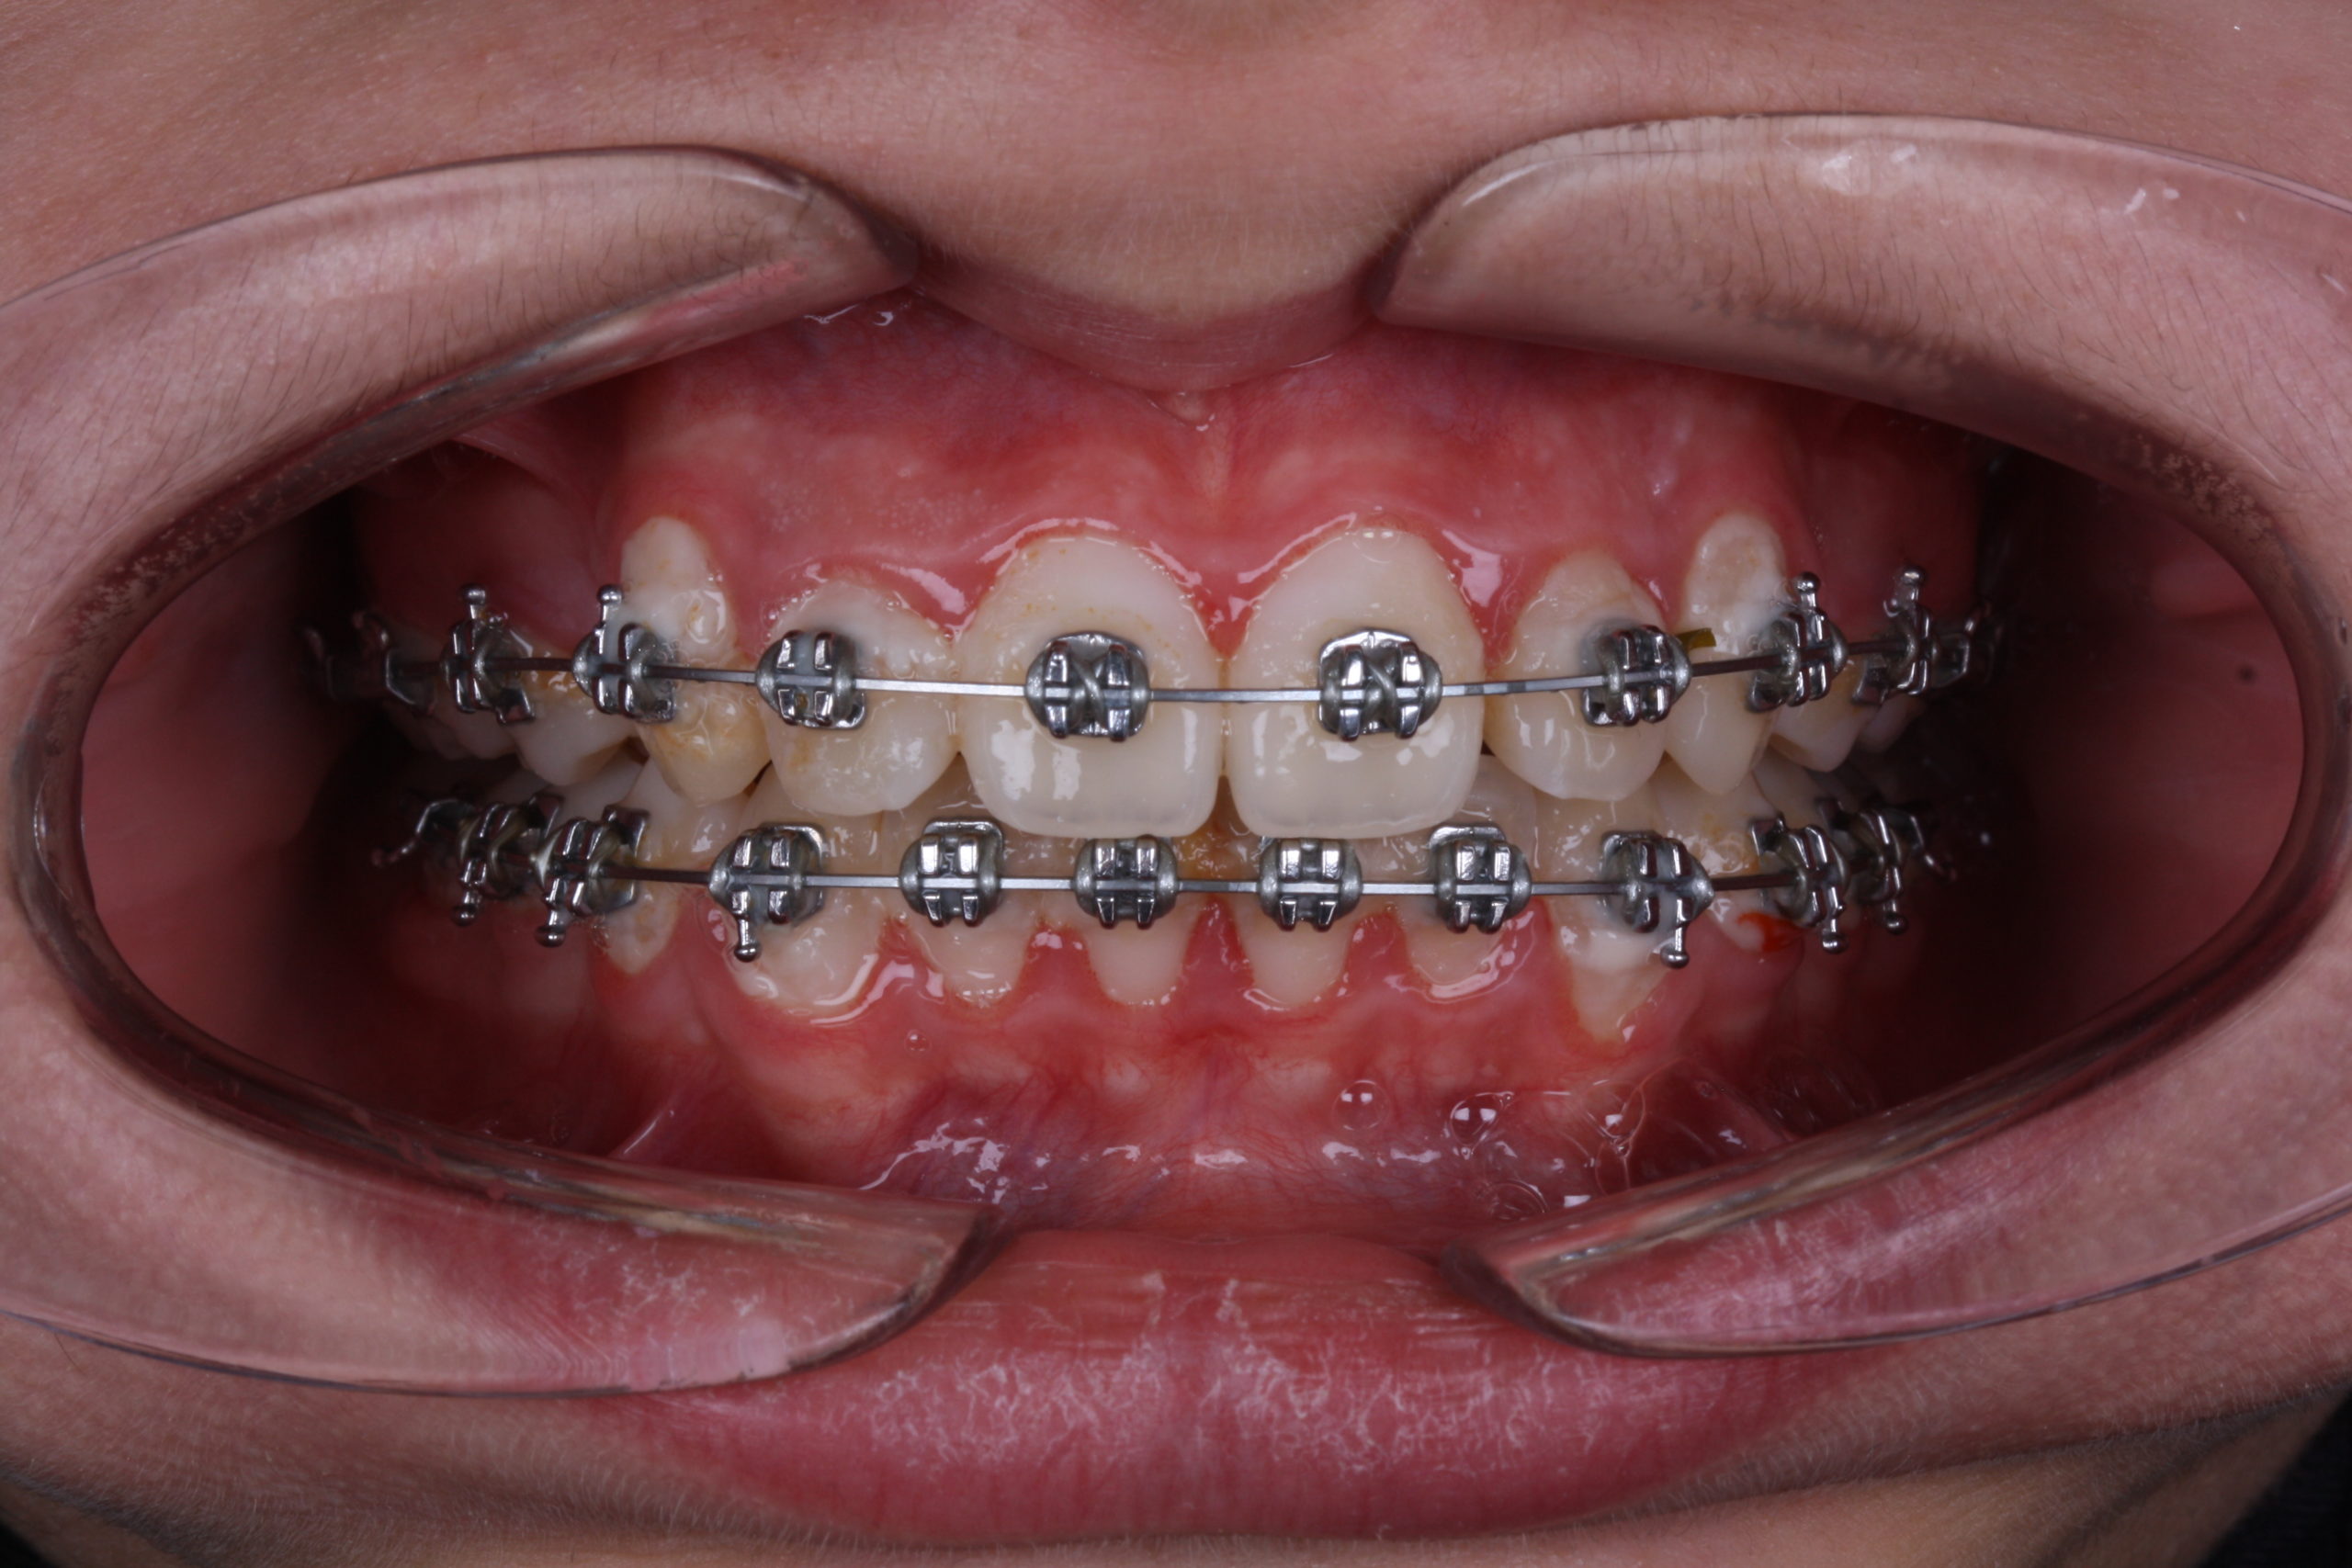

I haven’t used any device for anchorage control, just the braces. I’ve included upper second molars for anchorage. I’ve started with early light elastics for high canines. I applied IPR for lower teeth to help with the crowding. Treatment lasted 12 months.

I’ve used BioMax braces (MBT .022 slot) for this treatment. I choose BioMax for its unique and minimalist design. Patients with smaller teeth especially work well with BioMax.